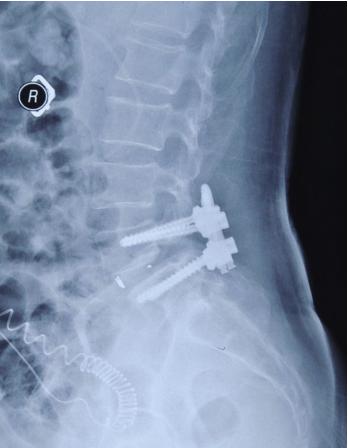

许多患者做脊柱手术都需要打钉子,这也变成患者们的困扰,尤其是术后复查拍片后,虽然看不懂片子,但那几颗明晃晃的钉子能看见。钉子毕竟不是体内原来的东西,这长在肉里有什么危害吗?还是需要取出来?那不是还要做一次手术?

做脊柱手术,我们放进体内的这种内置物,大家通常所说的“板子”、“螺钉”或者“钉棒系统”,要不要取出是视情况而定的。

绝大多数的内固定物,就是我们说的“钉子”,目前绝大部分都是钛合金的,钛合金本身的组织相容性特别好,它对机体的影响非常小,所以就算钉子不取,对机体也没有明显影响。所以对于椎体间进行了融合的患者,大多数情况下,不建议取内固定。